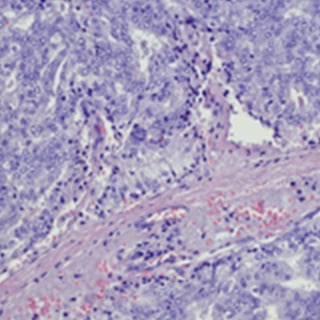

Early detection and diagnosis

We focus on finding prostate cancer early, when it's easier to treat. Our diagnostic team includes radiologists and pathologists with specialized training in genitourinary cancer. We offer some of the most sophisticated diagnostic technology available, including advanced prostate MRI and prostate-specific membrane antigen (PSMA) PET scan.